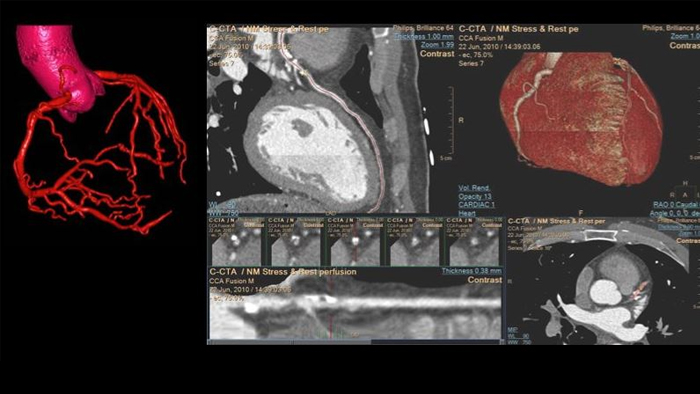

Unlock the full potential of CT as a non-invasive cardiac diagnostic tool.

See beyond routine cardiac imaging with the additional clinical information of Spectral CT for advanced cardiac applications. Learn how the Spectral CT 7500's "Always On" Spectral CT workflow helps you meet the needs of all your patients with zero compromises.